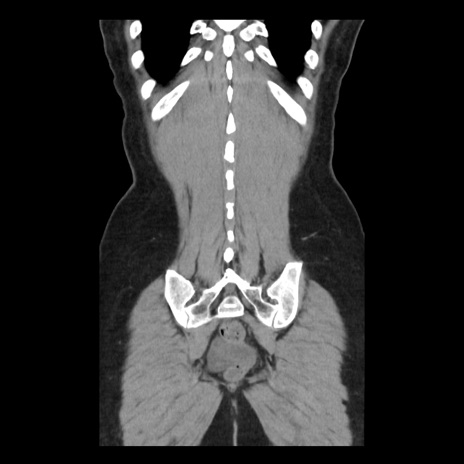

症例10(冠状断像)

【症例】 50歳代女性

【主訴】 腹痛

【現病歴】前日生レバーを食べた。今朝に排便あり。 昼前に突然発症の腹痛を生じ、当院救急外来を受診した。

【既往歴】 子宮筋腫にてで子宮全摘後

【身体所見】 意識清明、腹部:平坦、軟、下腹部やや左を中心に圧痛・反跳痛あり、筋性防御あり

【データ】WBC 7800、CRP 0.07